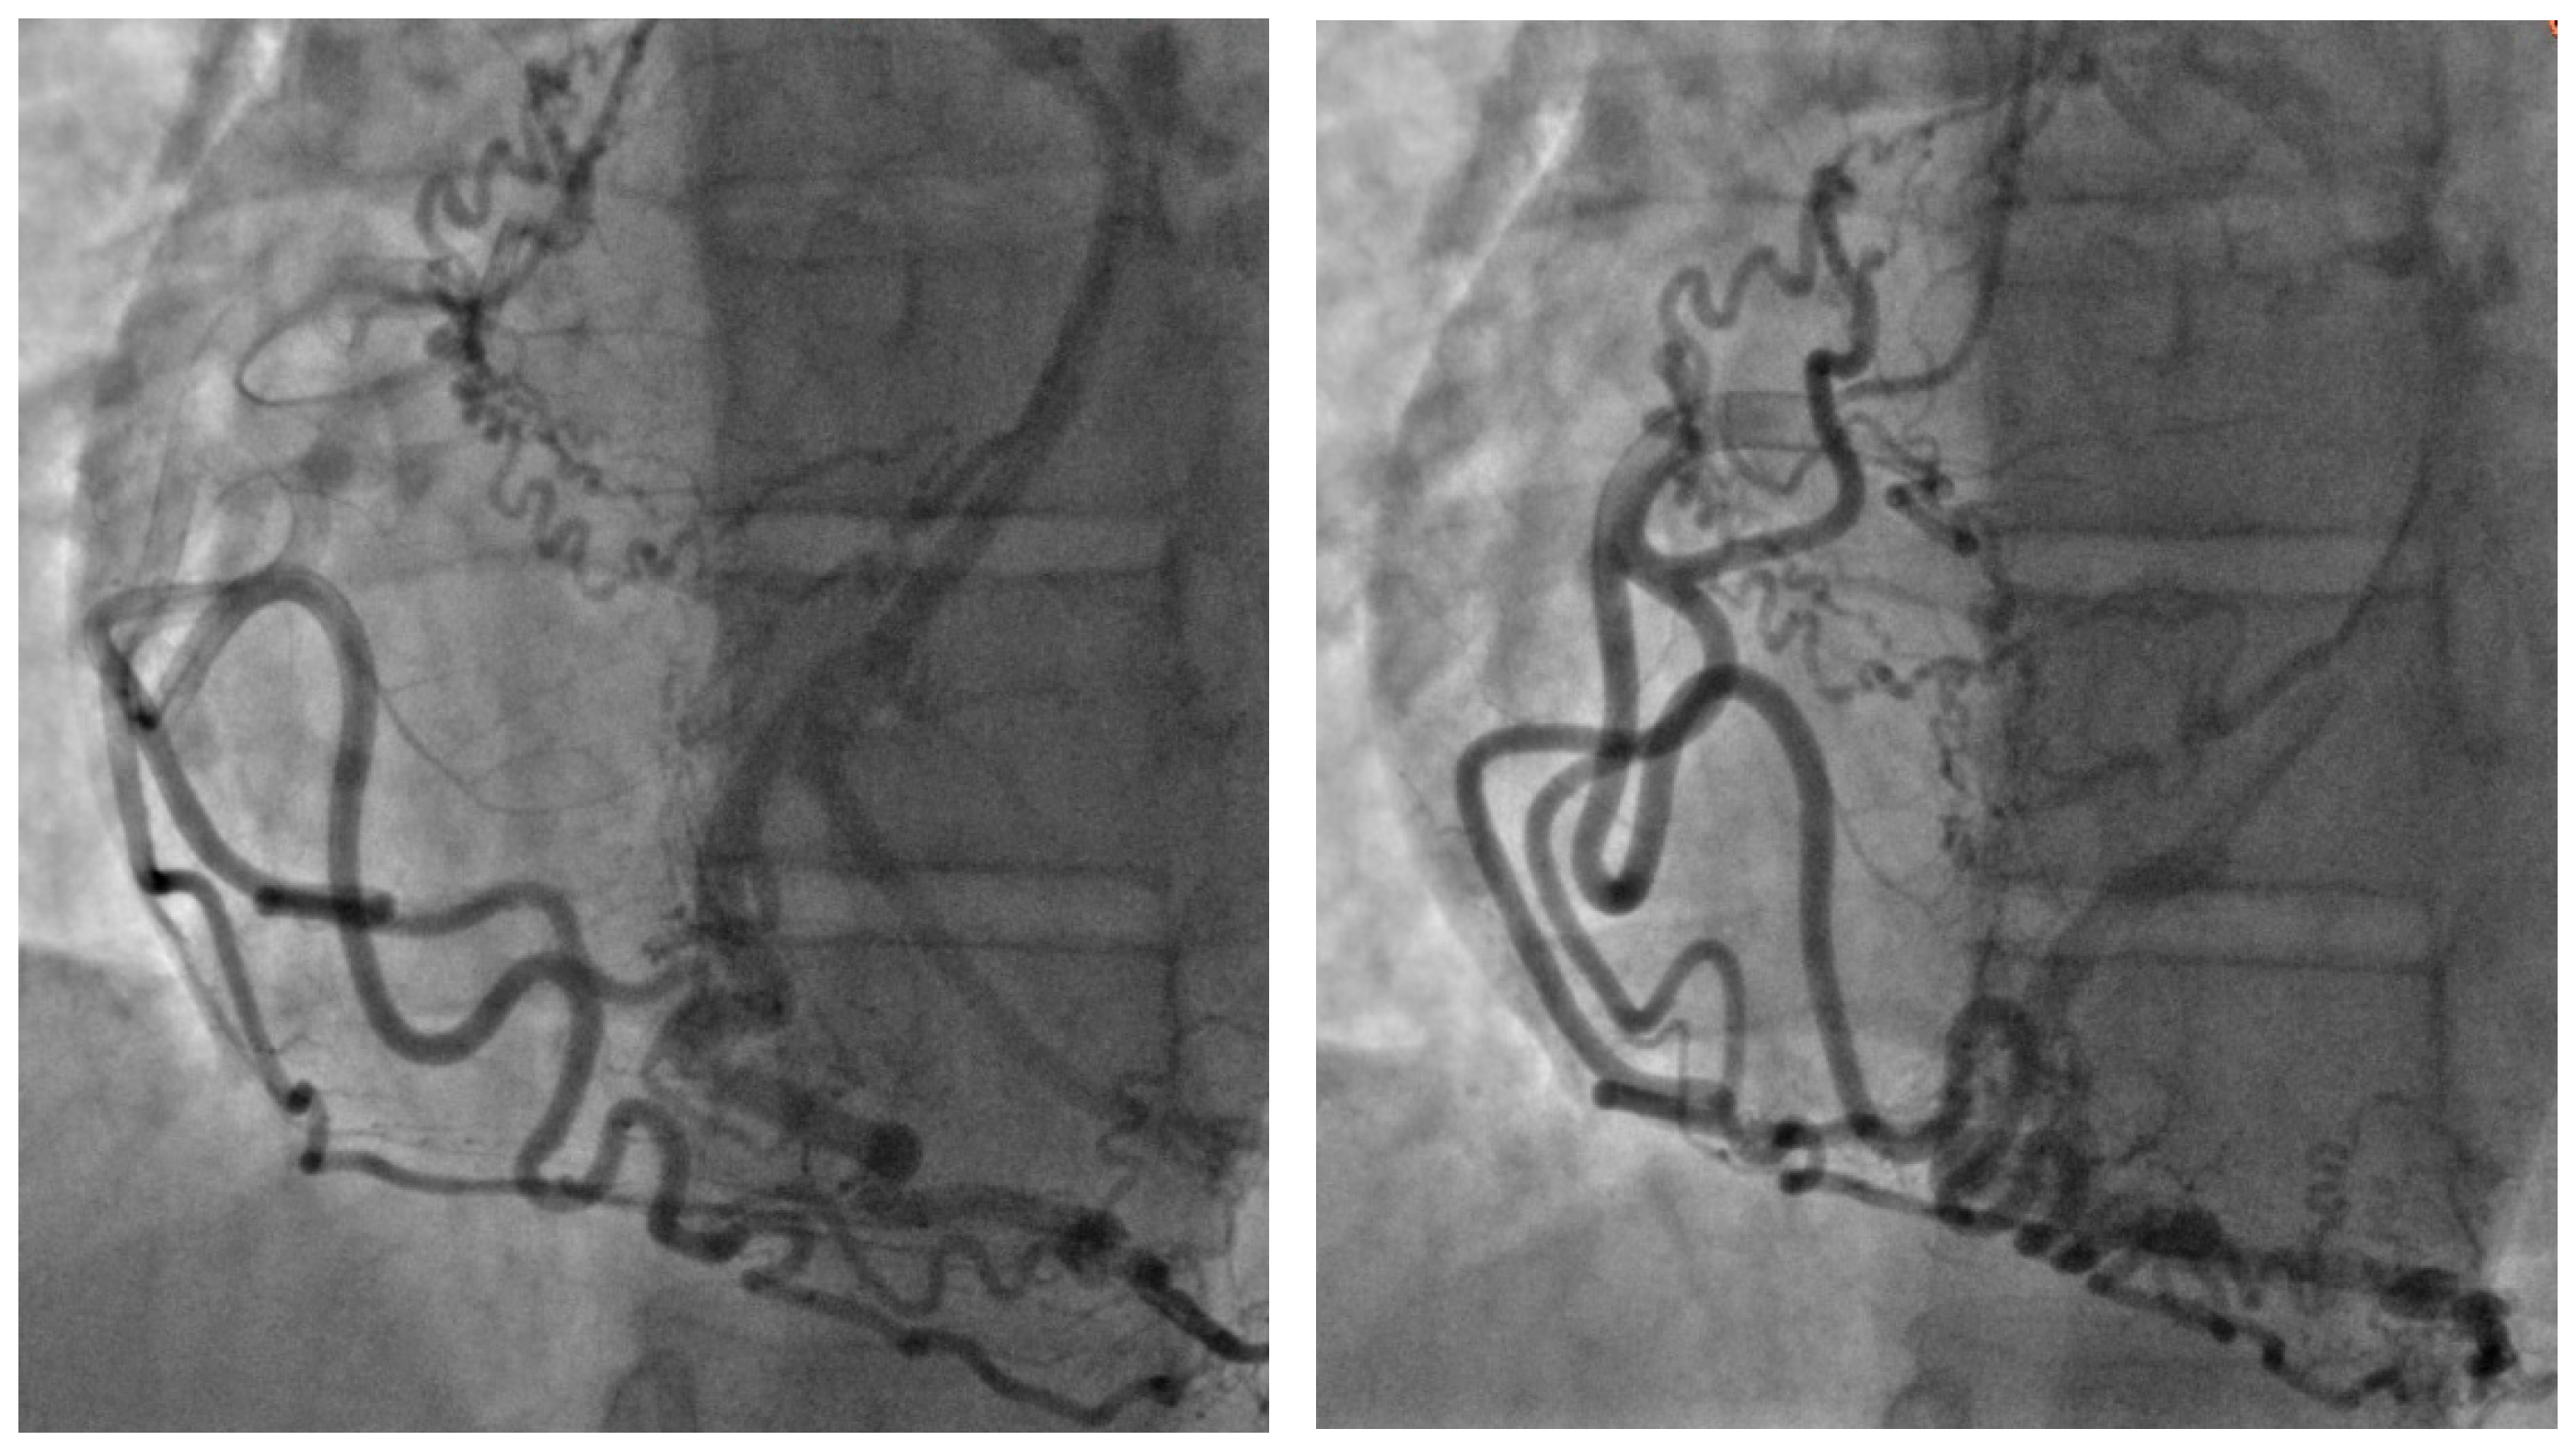

The coronary angiographic findings revealed no significant coronary artery stenosis. However, the procedure identified an anomalous and separate origin of the left coronary artery (LCA) from the right coronary cusp (RCC) (

Figure 1). Given the patient’s persistent symptoms and the angiographic findings, further evaluation was pursued. Multidetector computed tomography (MDCT) of the heart was performed, which confirmed the diagnosis of ALCAPA. The MDCT demonstrated coronary arteries originating from the RCC, including the left anterior descending coronary artery (LAD) with a coronary–pulmonary artery (PA) fistula, and an anomalous origin of the left circumflex (LCx) coronary artery from the right pulmonary artery (RPA) (